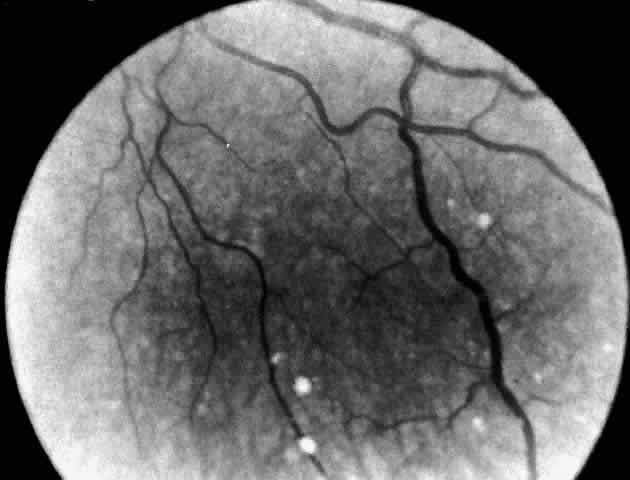

Electron microscopic examination of the cornea and retina showed the lipid stored was in the form of membranous cytoplasmic bodies (Fig. 7).68 The distribution of these inclusion bodies is similar to that of the birefringent material seen on light microscopy. The bodies are most abundant in retinal ganglion cells and retinal pigment epithelium. They are present in moderate numbers in corneal stromal cells, lens epithelium, corneal endothelium, vascular endothelium, and the sphincter muscle of the iris. They are infrequent in Müller cells, glial cells, and rod and cone inner segments.

Fig. 7. Retinal ganglion cell. (A) Portion of cell in Niemann-Pick disease, showing numerous membranous cytoplasmic bodies. Mitochondria (m) and dilated endoplasmic reticulum (er) are also evident. Area outlined in lower right is shown in greater magnification in B. (× 15,000) (B) Portion of cytoplasm of ganglion cell shown in A. Membranous cytoplasmic bodies cut in several different planes are evident, as are mitochondria (m) and endoplasmic reticulum (er) (×42,000). (Robb RM, Kuwabara T: The ocular pathology of type A Niemann-Pick disease: A light and electron microscopic study. Invest Ophthalmol 12:366, 1973)

The morphology of the membranous cytoplasmic bodies found in the eye in Niemann-Pick disease type A corresponds closely to the previously reported ultrastructure of lipid inclusions in the brain and viscera in other patients with Niemann-Pick disease type A. An ocular ultrastructural study of a 23-week-old fetus with Niemann-Pick disease type A also demonstrated rather extensive ocular involvement.69